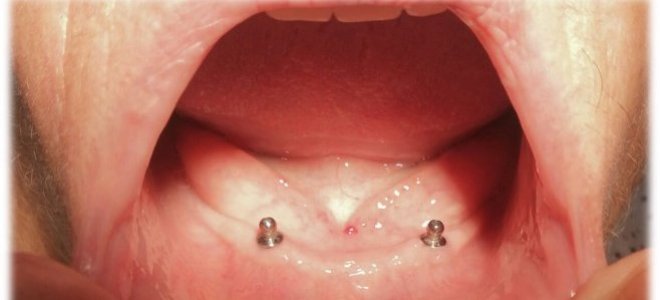

Muchos hombres y mujeres, que se encuentran con su maxilar inferior sin dientes, utilizan prótesis dentales con muy malos resultados debido a que sus condiciones anatómicas impiden que este aparato se retenga adecuadamente. Esta situación causa que las personas se aíslen socialmente, perdiendo su calidad de vida social y personal.

El odontólogo señaló que más de 30 personas ya se encuentran con sus implantes instalados y terminados, “y dentro de los próximos meses deberíamos terminar el proceso y llegar a los 300 beneficiados.  El efecto que tienen estos implantes desde el punto de vista social es muy importante, ya que estos pacientes no pueden portar sus prótesis por su condición anatómica y generalmente desaparecen de la vida social, se esconden de la familia y se aíslan de sus amigos. Estos implantes inferiores vienen al rescate de estos pacientes y lograr insertarlos nuevamente en la vida regular”.

En Quilpué los pacientes beneficiados serán 60, en Villa Alemana 50, en La Ligua 40, en Olmué 30, en Puchuncaví 20, en Petorca 20 y en Quillota 80, dando finalmente un total de 300 pacientes que recibirán este importante beneficio dental completamente gratuito y que mejorará su calidad de vida.